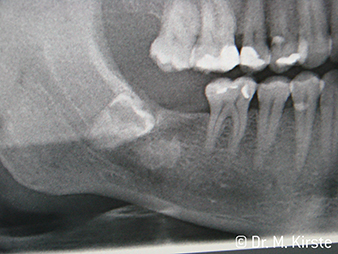

Radiographie W&H

Ill. 6 :

Exemple patient : la dent déplacée N° 48 …